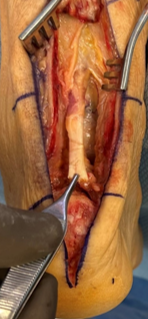

Following administration of general anesthesia, we placed a thigh tourniquet on the patient in prone position. A full-thickness longitudinal midline linear incision over the palpable dell extended distally over the posterior aspect of the calcaneus. We carried blunt dissection deeper to visualize the full-thickness tear (Figure 3). Next, we harvested the flexor hallucis longus (FHL) tendon using the short harvest technique (Figure 4). Subsequently, we remodeled the posterior aspect of the calcaneus to remove any underlying pathology.